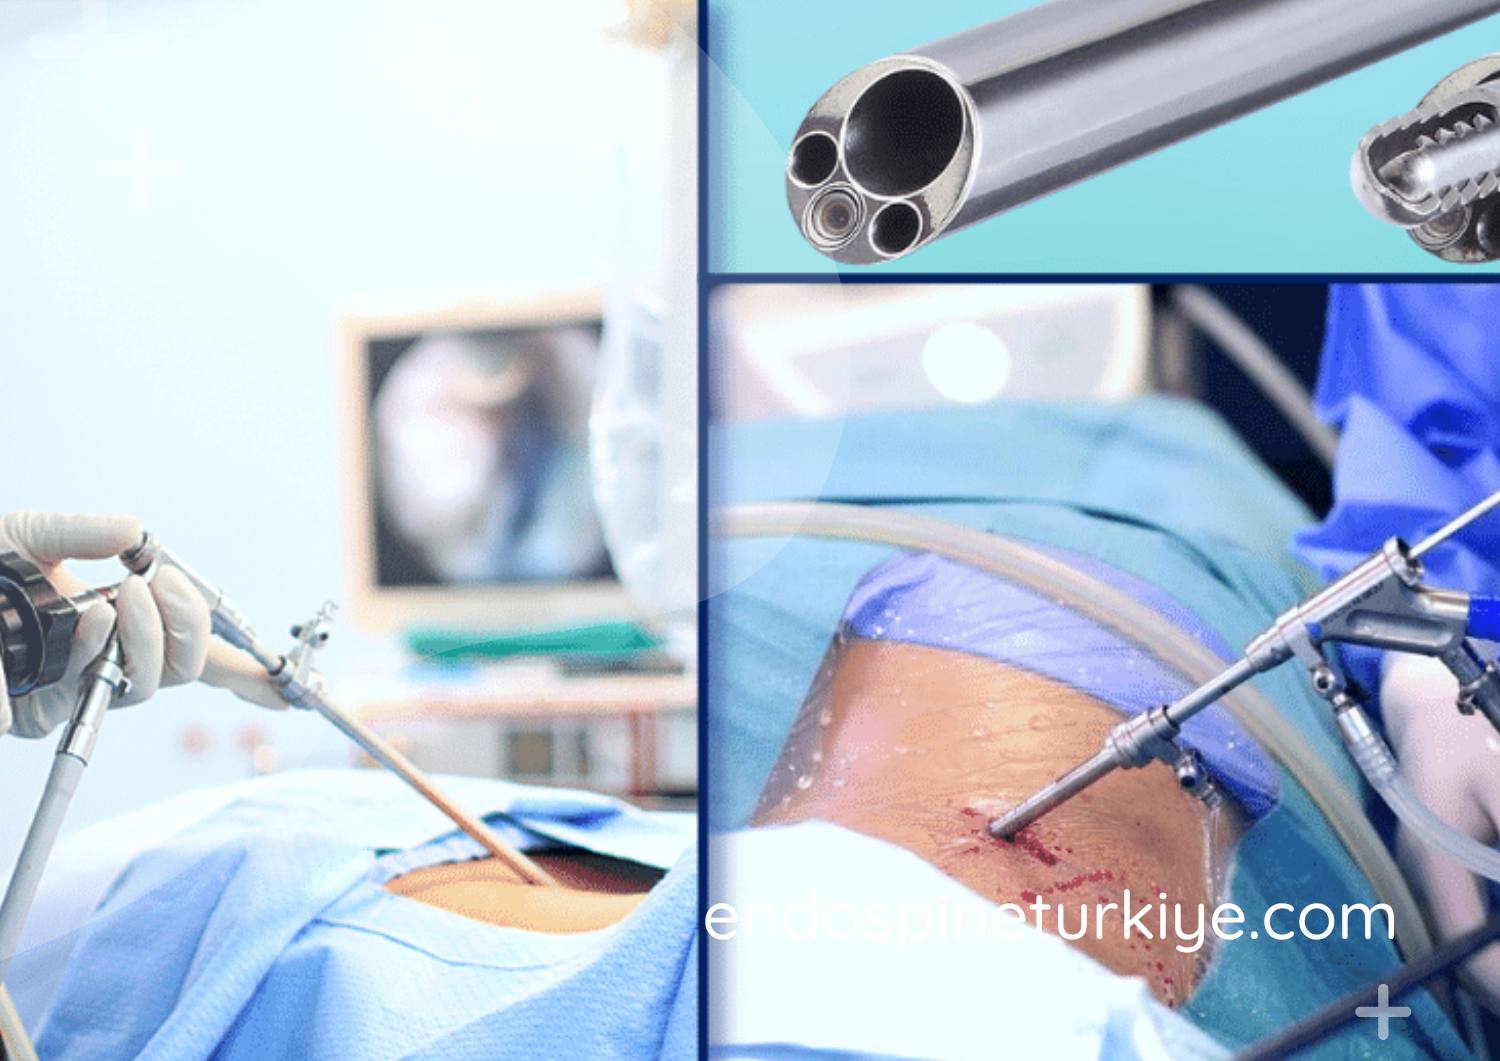

PELD (Perkütan Endoskopik Lomber Diskektomi), bel fıtığı cerrahisinde kullanılan en ileri tam kapalı endoskopik ameliyat tekniğidir. 6mm'lik mikroskobik bir açıklıktan, özel HD endoskop aracılığıyla fıtıklaşan disk materyali alınır ve baskı altındaki sinir rahatlatılır.

Bu kapalı cerrahi tekniğinde kas dokusu kesilmez, kemik yapıya dokunulmaz. Hasta ameliyat gününde mobilize edilir ve bir sonraki gün taburcu olur. Lokal anestezi seçeneğiyle birlikte genel anesteziyle ilişkili riskler tamamen bertaraf edilir.

Endoskopik Cerrahi

6mm'lik açıklıktan endoskop konumlandırılır, HD görüntüleme altında fıtık materyali uzaklaştırılır.